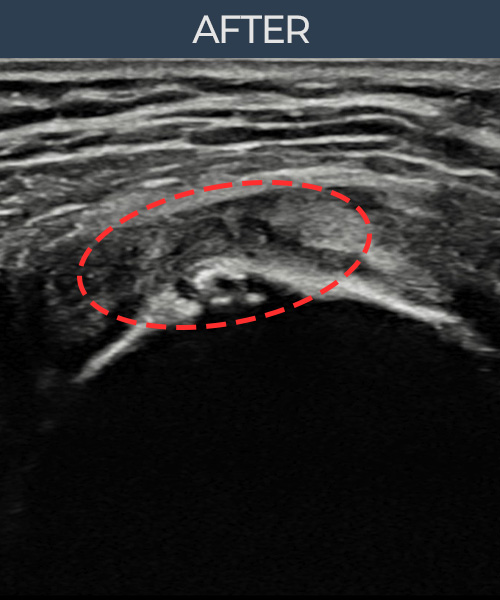

비수술 치료 전후사진

비수술로도 파열된 인대를

물리적으로 재건해 드립니다

플래티넘정형외과에서는 수술없이도 물리적으로

파열된 인대를 재건

하는것이 가능합니다.